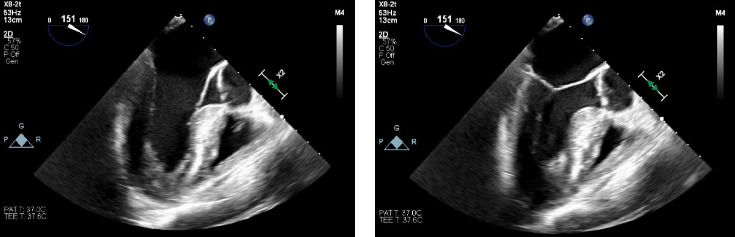

Abstract Image